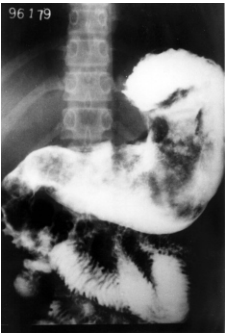

Analise o seguinte exame contrastado do estômago, realizado em uma paciente com queixas de dor hipogástrica há 2 meses.

Enunciado 172252-1

Com base no exposto anteriormente, é correto afirmar que o exame